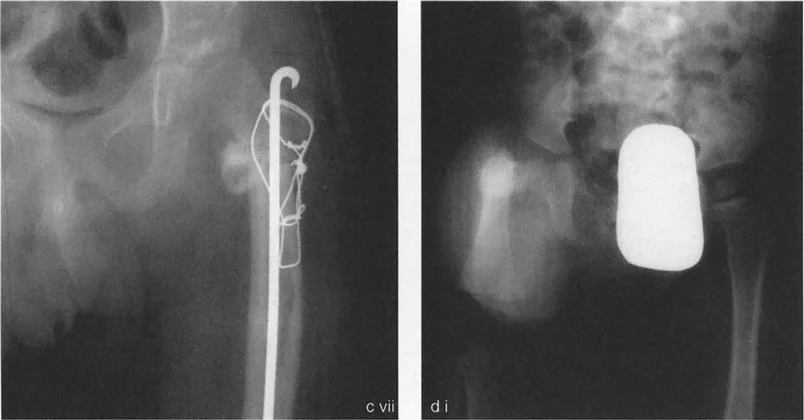

جراحة عظم الفخذ الروحاء (Varus Osteotomy) لتصحيح الورك الروحاء (Valgus Deformity)

تُجرى هذه الجراحة عندما يكون عنق الفخذ مائلاً جدًا للأعلى (الورك الروحاء). تهدف العملية إلى تقليل زاوية عنق الفخذ، مما يجعلها أكثر أفقية.

• التقنية: تتطلب الجراحة قدرة كافية على تبعيد رأس الفخذ. عادةً ما لا تحد عضلات المقربة من تبعيد الجزء القريب من الفخذ بعد قطع العظم لأنها ترتبط بعيدًا عن مستوى قطع العظم.

• تأثير التقصير: تؤدي جراحة عظم الفخذ الروحاء إلى تقصير في طول الساق، مما يريح عضلات المقربة ويقلل الحاجة إلى بضع وتر المقربة.

• القيود داخل المفصل: إذا كان تحديد التبعيد ناتجًا عن عوامل داخل المفصل، فقد يتطلب الأمر بضع كبسولة وتحرير داخل المفصل. إذا كان السطح المفصلي مشوهًا، فقد لا يمكن تحقيق التصحيح الكامل إلا بعد إعادة تشكيل رأس الفخذ.

• مستويات القطع: يمكن أن يكون القطع فوق المدور الصغير (Intertrochanteric) أو تحته (Subtrochanteric).

• جراحة عظم الفخذ الروحاء: إذا كان القطع فوق المدور الصغير، فإنه يميل إلى إرخاء الوتر. إذا كان القطع تحت المدور الصغير، فإنه يشد الوتر، مما يزيد من صعوبة الإجراء.

• لذلك، يفضل الأستاذ الدكتور محمد هطيف إجراء جراحة عظم الفخذ الروحاء فوق المدور الصغير، وجراحة عظم الفخذ الفحجاء تحت المدور الصغير، لتحسين النتائج وتسهيل الجراحة.